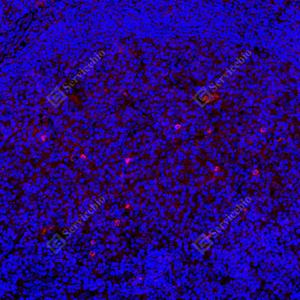

| IF检测Smad2蛋白(货号 GB15511)(红色). 样品: 人扁桃体, 4%多聚甲醛 (货号G1101) 固定12-24小时. 抗原修复: 抗原修复仪(货号 ARI-4),Tris-EDTA抗原修复液(pH 9.0) (货号G1203), 水浴100℃, 25分钟. 封闭: 3% BSA(货号GC305010)的PBS溶液, 室温孵育30分钟. —抗: 1: 400稀释, 4℃ 孵育过夜. 二抗: Cy3标记山羊抗兔IgG (H+L) (货号GB21303), 1: 300稀释, 室温孵育1小时. |